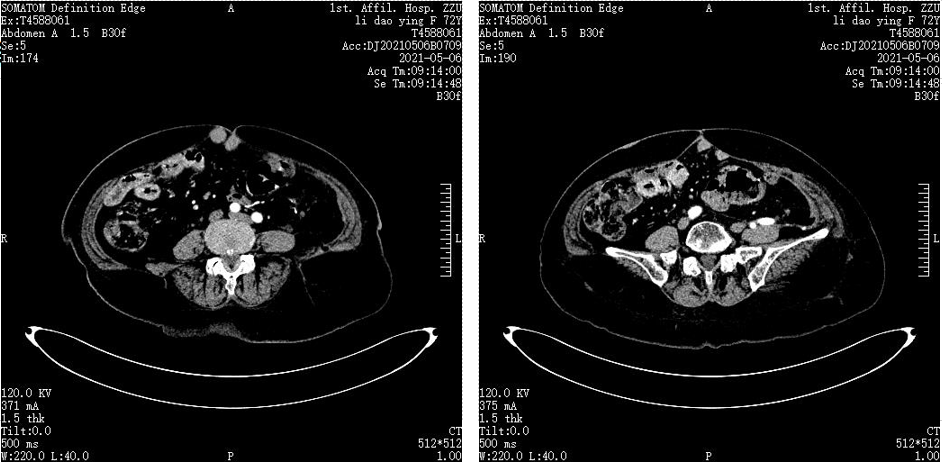

当时我中心正在进行恩沃利单抗II期临床试验,该患者的基因检测结果显示为MSI-H,于2019年2月通过筛选后该患者入组“恩沃利单抗治疗dMMR/MSI-H 晚期结直肠癌及其他晚期实体瘤患者的临床疗效和安全性的多中心II期临床研究”。2019年3月起,为患者进行恩沃利单抗150mg,皮下注射,QW治疗,2019年5月7日复查CT显示,病灶显著缩小,疗效评估为部分缓解(PR)。该患者半年后复查CT提示腹壁及腹腔结节几乎完全消失,疗效评估为CRu。

图片

图3.2019年2月22日入组前CT

图4.2019年5月7日复查CT